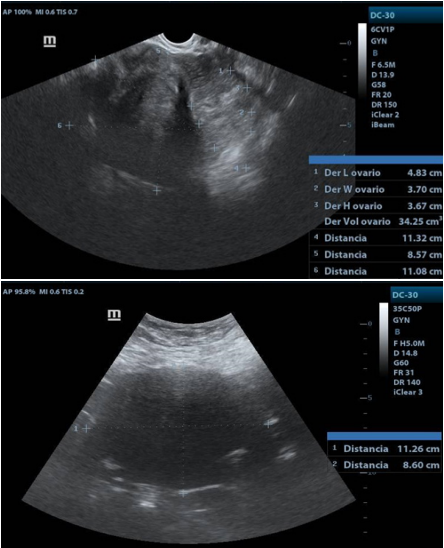

Transvaginal USG: uterus in AVF 4.5x5x3.3cm, LE 12.3mm. Right ovary: 4.8x3.6x3.7 cm vol. 34cc, with a tumor measuring 11.2x8.6cm, solid, with homogeneous and hypoechoic echotexture, with posterior acoustic shadow and Doppler flow uptake. Left ovary: 5x5x2.2cm vol. 19.6cc.

USG Transvaginal

1. Right adnexa, with heterogeneous image, hypoechoic mass, with clear border. with distance of 11.26X11X8.6cms.

1. Acoustic attenuation posterior a hypecoic mass en right adnexa.